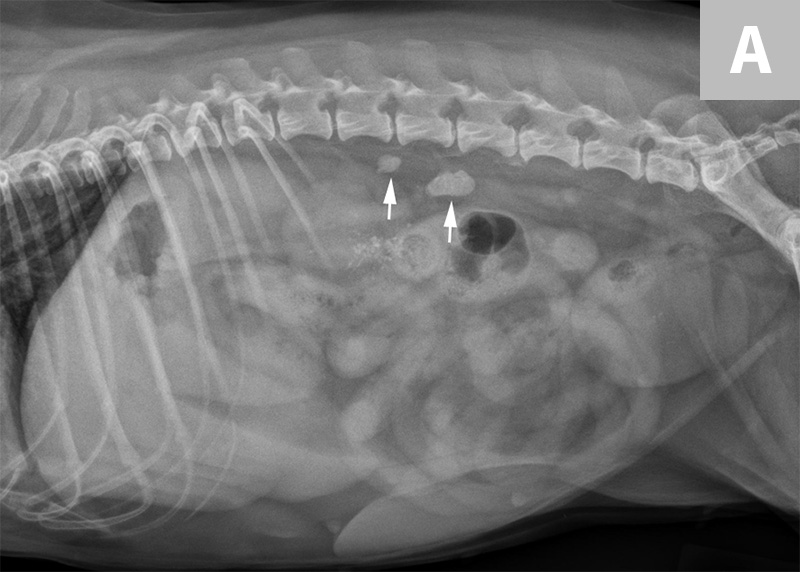

Managing Urolithiasis in Dogs Today s Veterinary Practice outlet, Bladder Stones in Dogs outlet, Managing Urolithiasis in Dogs Today s Veterinary Practice outlet, Bladder Stones in Dogs outlet, Why you see them why you don t Radiographs and uroliths outlet, Find Those Urinary Bladder Stones New Vet Equipment outlet, Bladder Stones in Dogs outlet, Urolith Center outlet, Lateral abdominal radiograph of a male entire Rottweiler dog. The outlet, Struvite Stones Canine Mar Vista Animal Medical Center outlet, Bladder Stones in Dogs outlet, Urolithiasis in Small Animals Urinary System Merck Veterinary outlet, Imaging of Calculi of the Urinary System outlet, Bladder Stones in Dogs outlet, Bladder Stones in Canines outlet, Ammonium Urate Urolithiasis outlet, Bladder Stones in Dogs Diagnosis and Treatment PetCoach outlet, Bladder Stones in Dogs outlet, Imaging of Calculi of the Urinary System outlet, Cystotomy to Remove Urolith Wellness Veterinary Hospital outlet, A less usual case of canine urolithiasis Companion Animal outlet, Evaluation of a dry therapeutic urinary diet and concurrent outlet, Urinary Stones outlet, Find Those Urinary Bladder Stones New Vet Equipment outlet, Why you see them why you don t Radiographs and uroliths outlet, Evaluation of a dry therapeutic urinary diet and concurrent outlet, Treatment and Prevention of Kidney and Bladder Stones Whole Dog outlet, Imaging of Calculi of the Urinary System outlet, Urolithiasis in Small Animals Urinary System Merck Veterinary outlet, Diet for Dogs with Urate Stones Elmo s Kitchen outlet, Bladder Stones in Dogs Complete Guide Emergency Vet 24 7 outlet, Cystotomy to Remove Urolith Wellness Veterinary Hospital outlet, Different Types of Bladder Stones in Dogs Dog Discoveries outlet, Ventro dorsal abdominal X ray showing bilateral kidney enlargement outlet, DogAware Articles Urate Cystine and Less Common Urinary Stones outlet.